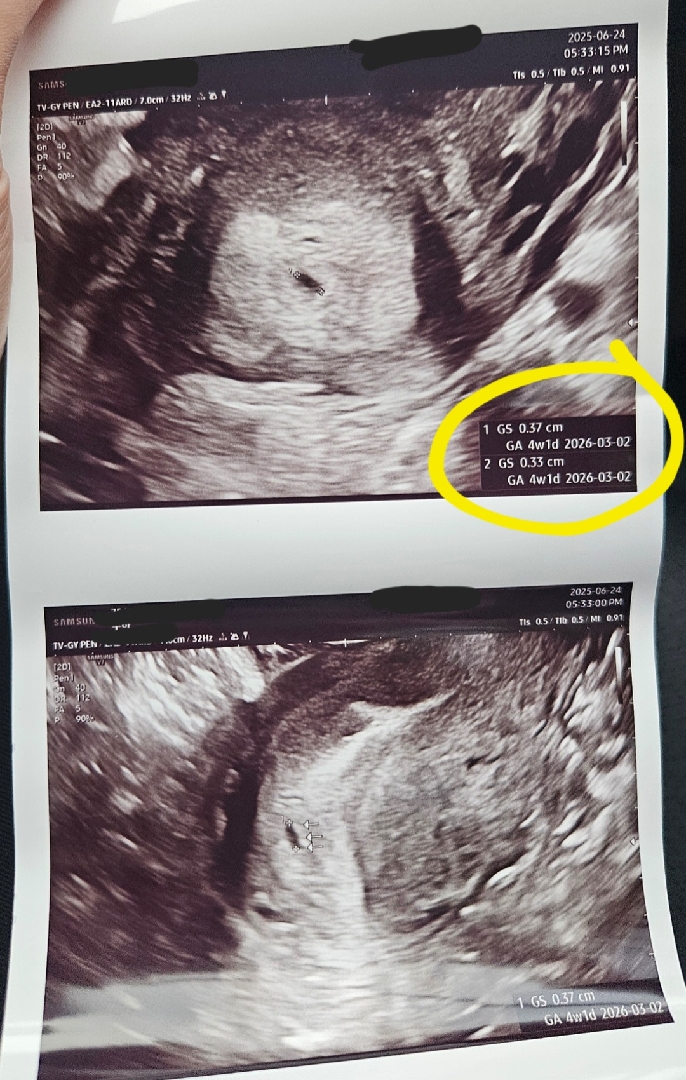

집에 와서 다시 초음파 사진을 봤는데 아기 집이 두 개 있는 것처럼 보여요 🫣그런데 병원에서는 의사 선생님이 그런 말씀은 안 하셨어요.. 그리고 1 GS, 2 GS 적혀있어서 더 궁금해요 ㅎㅎ 이기집 아니면 뭘까용

네 그런 것 같아요 🤭다음 진료 때까지 기다려야 할 것 같아요🙏